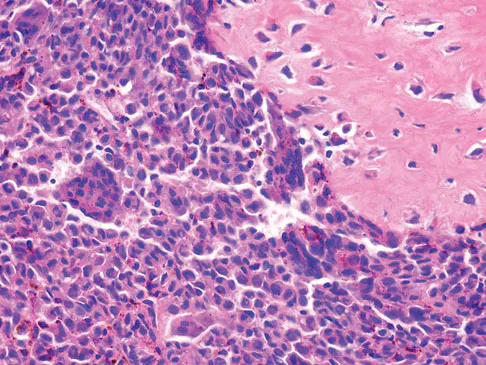

A 13-year-old girl has had increasing left hip pain for the past 4 months. A radiograph, bone scan, MRI scan, and photomicrograph are shown in Figures 1a through 1d. Which of the following immunohistochemistry results would confirm the most likely diagnosis?

A 16-year-old boy has had left knee pain and swelling after sustaining a minor twisting injury while playing basketball 2 weeks ago. Figures 5a through 5e show the radiograph, MRI scans, and biopsy specimens. What is the most likely diagnosis?

Figures 12a through 12e show the radiograph, MRI scans, and biopsy specimens of a 17-year-old boy. What is the most likely diagnosis?